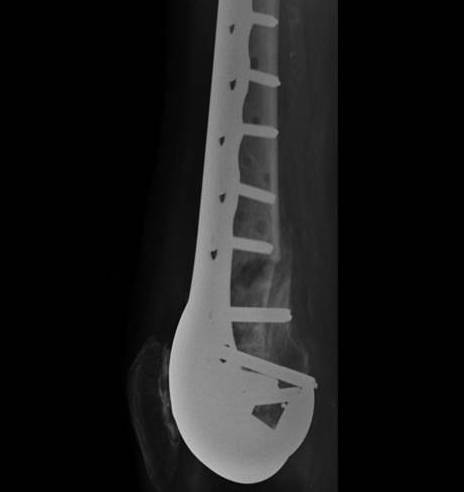

TKR Periprosthetic Fracture Minimall Dislplaced CTTKR Periprosthetic Fracture Locking Plate APTKR Periprosthetic Fracture Locking Plate Lateral

Technique

Minimally invasive technique

- may need unicortical screws distally

Results

Kolb et al J Trauma 2010

- 19 patients treated with LISS plate

- 2 delayed union

- otherwise good union rate with minimal complications and good ROM

Streubel JBJS Br 2010

- compared proximal fractures to distal (beyond the femoral prosthesis)

- showed similar healing rates in each group treated with locking plates